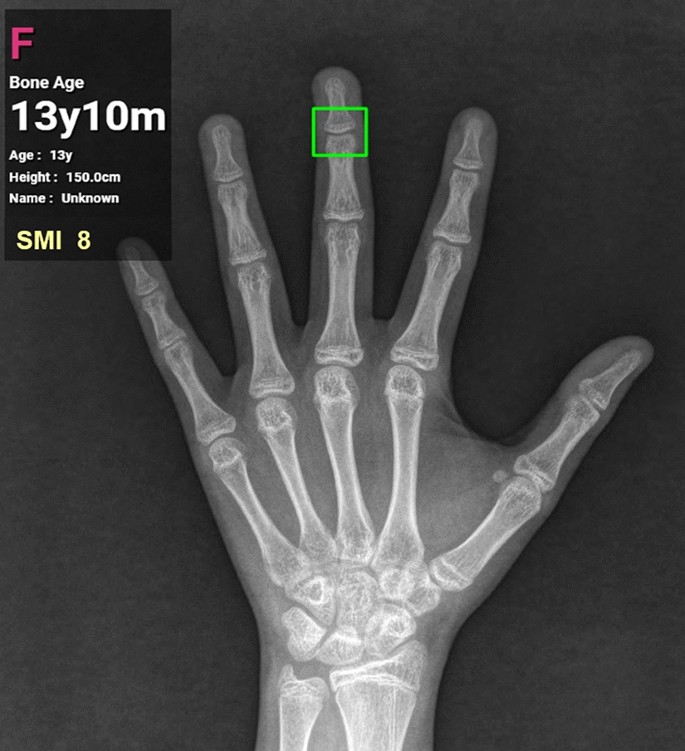

In addition to the major areas of growth plate evaluated for the TW3 method and the carpal region, all regions subject to the evaluation of SMI were included as ROIs (Fig. 2). In particular, MP5 (fifth middle phalanx) and PP1 (first proximal phalanx) were added by utilizing the detection algorithm based on the work by Li et al.13 RetinaNet, a deep convolutional neural network (CNN), was utilized for the automated detection of ROIs. Subsequently, each of the detected regions was analyzed for skeletal maturity level based on the morphological changes, such as epiphyseal widening, presence of sesamoid, epiphyseal capping and epiphyseal fusion. For image classification a vision transformer-based deep learning model was utilized. The final skeletal age was calculated by analyzing and integrating the probability of skeletal maturity of each area. Irrespective of the skeletal age prediction, skeletal maturity level of each of the six regions relevant for SMI evaluation was analyzed for SMI stage mapping. The final SMI stage was calculated by integrating the skeletal maturity and age of each ROI, and the final skeletal age. Both SMI and skeletal age were outputted as results (Fig. 3).